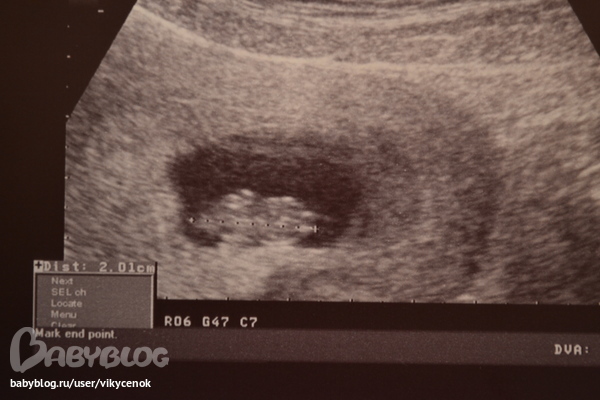

как только начали смотреть,он начал капошиться и ручками помахивать своими крошечными,так здорово))))))скажите,а где формируется сейчас у него голова,просто с врачом спорила,я говорю,что голова,если смотреть на фото,то справа,большая,вдны зачатки ручек,а внизу (слева)ножки его!!

она говорит наоборот,маленькое-голова,большая-попа типа)))))))))

По мне, так голова справа и вообще, он к нам спинкой (как мне кажется) лежит, лапусик

Спасибо,дорогая!видишь справа 2 белых полоски?мне сказали это ножки!!!а я все думаю что справа голова!не знаю:(

Мне кажется это "шумы", на ножки не особо похожи. А голова все равно справа!))) Ну ничего, главное, что малыш здоров, а с какой стороны голова на УЗИ не так и важно)

Вот мы на 9ой неделе, но у нас голова справа